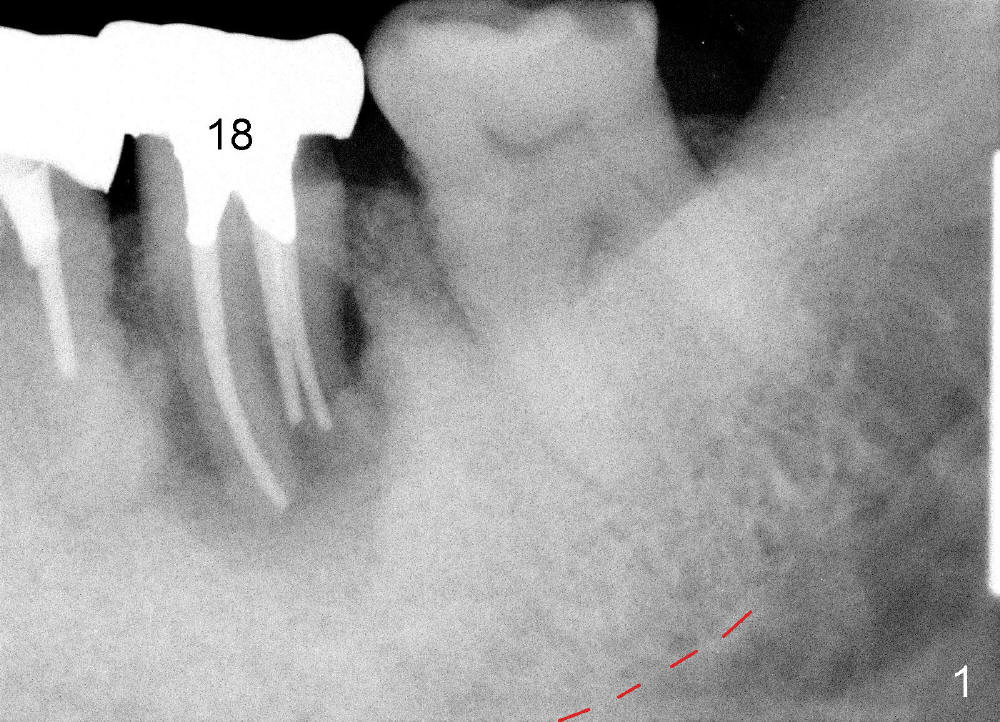

A 84-year-old man has severe pain distal to #18 (Fig.1). The affected tooth is planned to be restored by a 7x17 mm implant (Fig.2).

When the tooth is extracted, the socket is extremely large. The largest tapered tap (8x17 mm) basically drops into the socket; it is not stable in the socket (Fig.3). It appears necessary to engage into the nascent bone, which is 8.37 mm long.